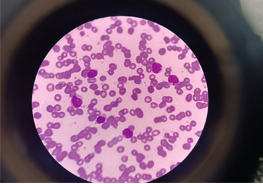

A well-recognized Pediatric Medical oncologist and hematologist practicing in New Delhi. In my career of 20 years in this field of pediatric Medical oncology and hematology, I have treated all kinds of hematological and solid cancers and have a keen interest in neuro-oncology. I have done more than 150 bone marrow transplant in last 8 years for both non- malignant and malignant conditions like thalassemia, aplastic anemia,, metabolic disorders, leukemias, lymphomas, Ewing’s sarcoma, brain tumors, neuroblastoma etc.

Pediatric Hematology